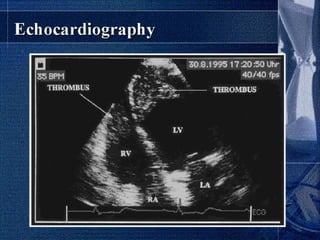

Echocardiography

Echocardiography is a useful tool when making the

diagnosis of EMF and has been demonstrated to

successfully differentiate EMF and other processes.

The presence and location of fibrosis as determined by

echocardiography correlates well with autopsy findings.

Findings include thickening of the inferior and basal

left ventricular wall, apical obliteration, thrombi

adherent to endocardial surface, mitral regurgitation,

and tricuspid regurgitation.

A pericardial effusion is frequently present and may

be large.

Diastolic function by Doppler echocardiography tend to

correlate with the functional status of the patient.

most patients present with later stages of EMF, a

restrictive filling pattern in the left ventricular

outflow tract is most common.

Recently, decreased flow propagation velocity (Vp)

Color-flow imaging frequently exhibits tricuspid and

mitral regurgitation.

Spectral Doppler analysis of tricuspid regurgitation

frequently reflects an increased pulmonary artery

systolic pressure.